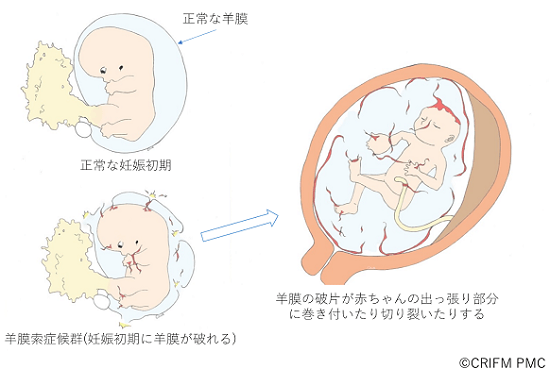

胎児の病気について クリフム出生前診断クリニック